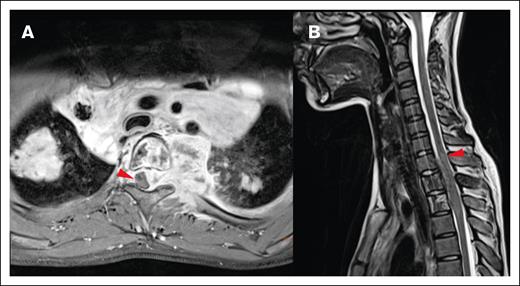

Local impact on CNS structures. (A) Displacement and mild compression of spinal cord to the right without contrast enhancement in the transverse T1 fat saturated image. (B) The same patient with edema clearly visible in the spinal cord in a sagittal T2-weighted MRI image.